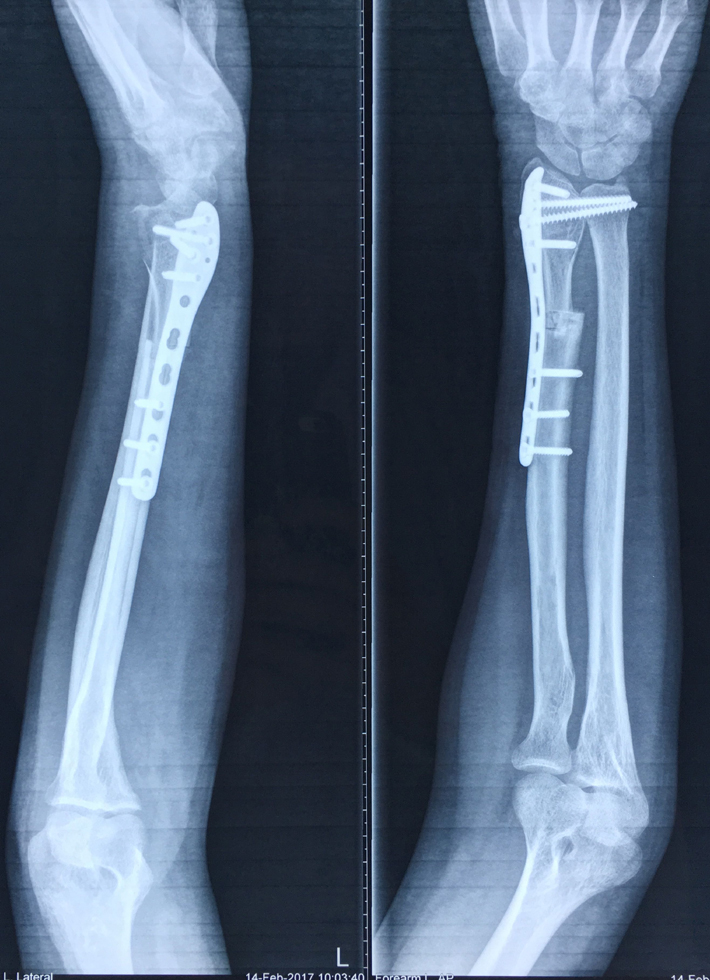

近日,我院关节与骨肿瘤科为一名桡骨远端骨巨细胞瘤Ⅲ级、肿瘤突破间室的男性患者成功实施了肿瘤广泛切除,自体腓骨活骨移植重建桡腕关节术。据悉,对于肢体恶性、侵袭性骨肿瘤,实行广泛外科边界的切除是达到良好的肿瘤学疗效的基础,但这必然会带来肢体结构和功能的更多的丧失。如何既能达到肿瘤的广泛切除,又能最大限度恢复肢体的结构和功能是骨肿瘤外科所追求的目标。肢体结构和功能的生物重建是最接近肢体生理状态的长期有效的重建方式。该方法要求手术者不仅具有精湛的肿瘤外科技术,还要有熟练的显微外科技术,是目前临床上受到普遍推崇的方法。近年来,关节与骨肿瘤科已开展此类手术20多例,取得了良好的效果。